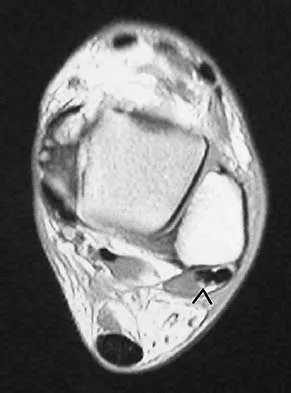

Figure 24 shows an axial MRI scan of the ankle. The arrowhead is pointing to what structure?

Explanation